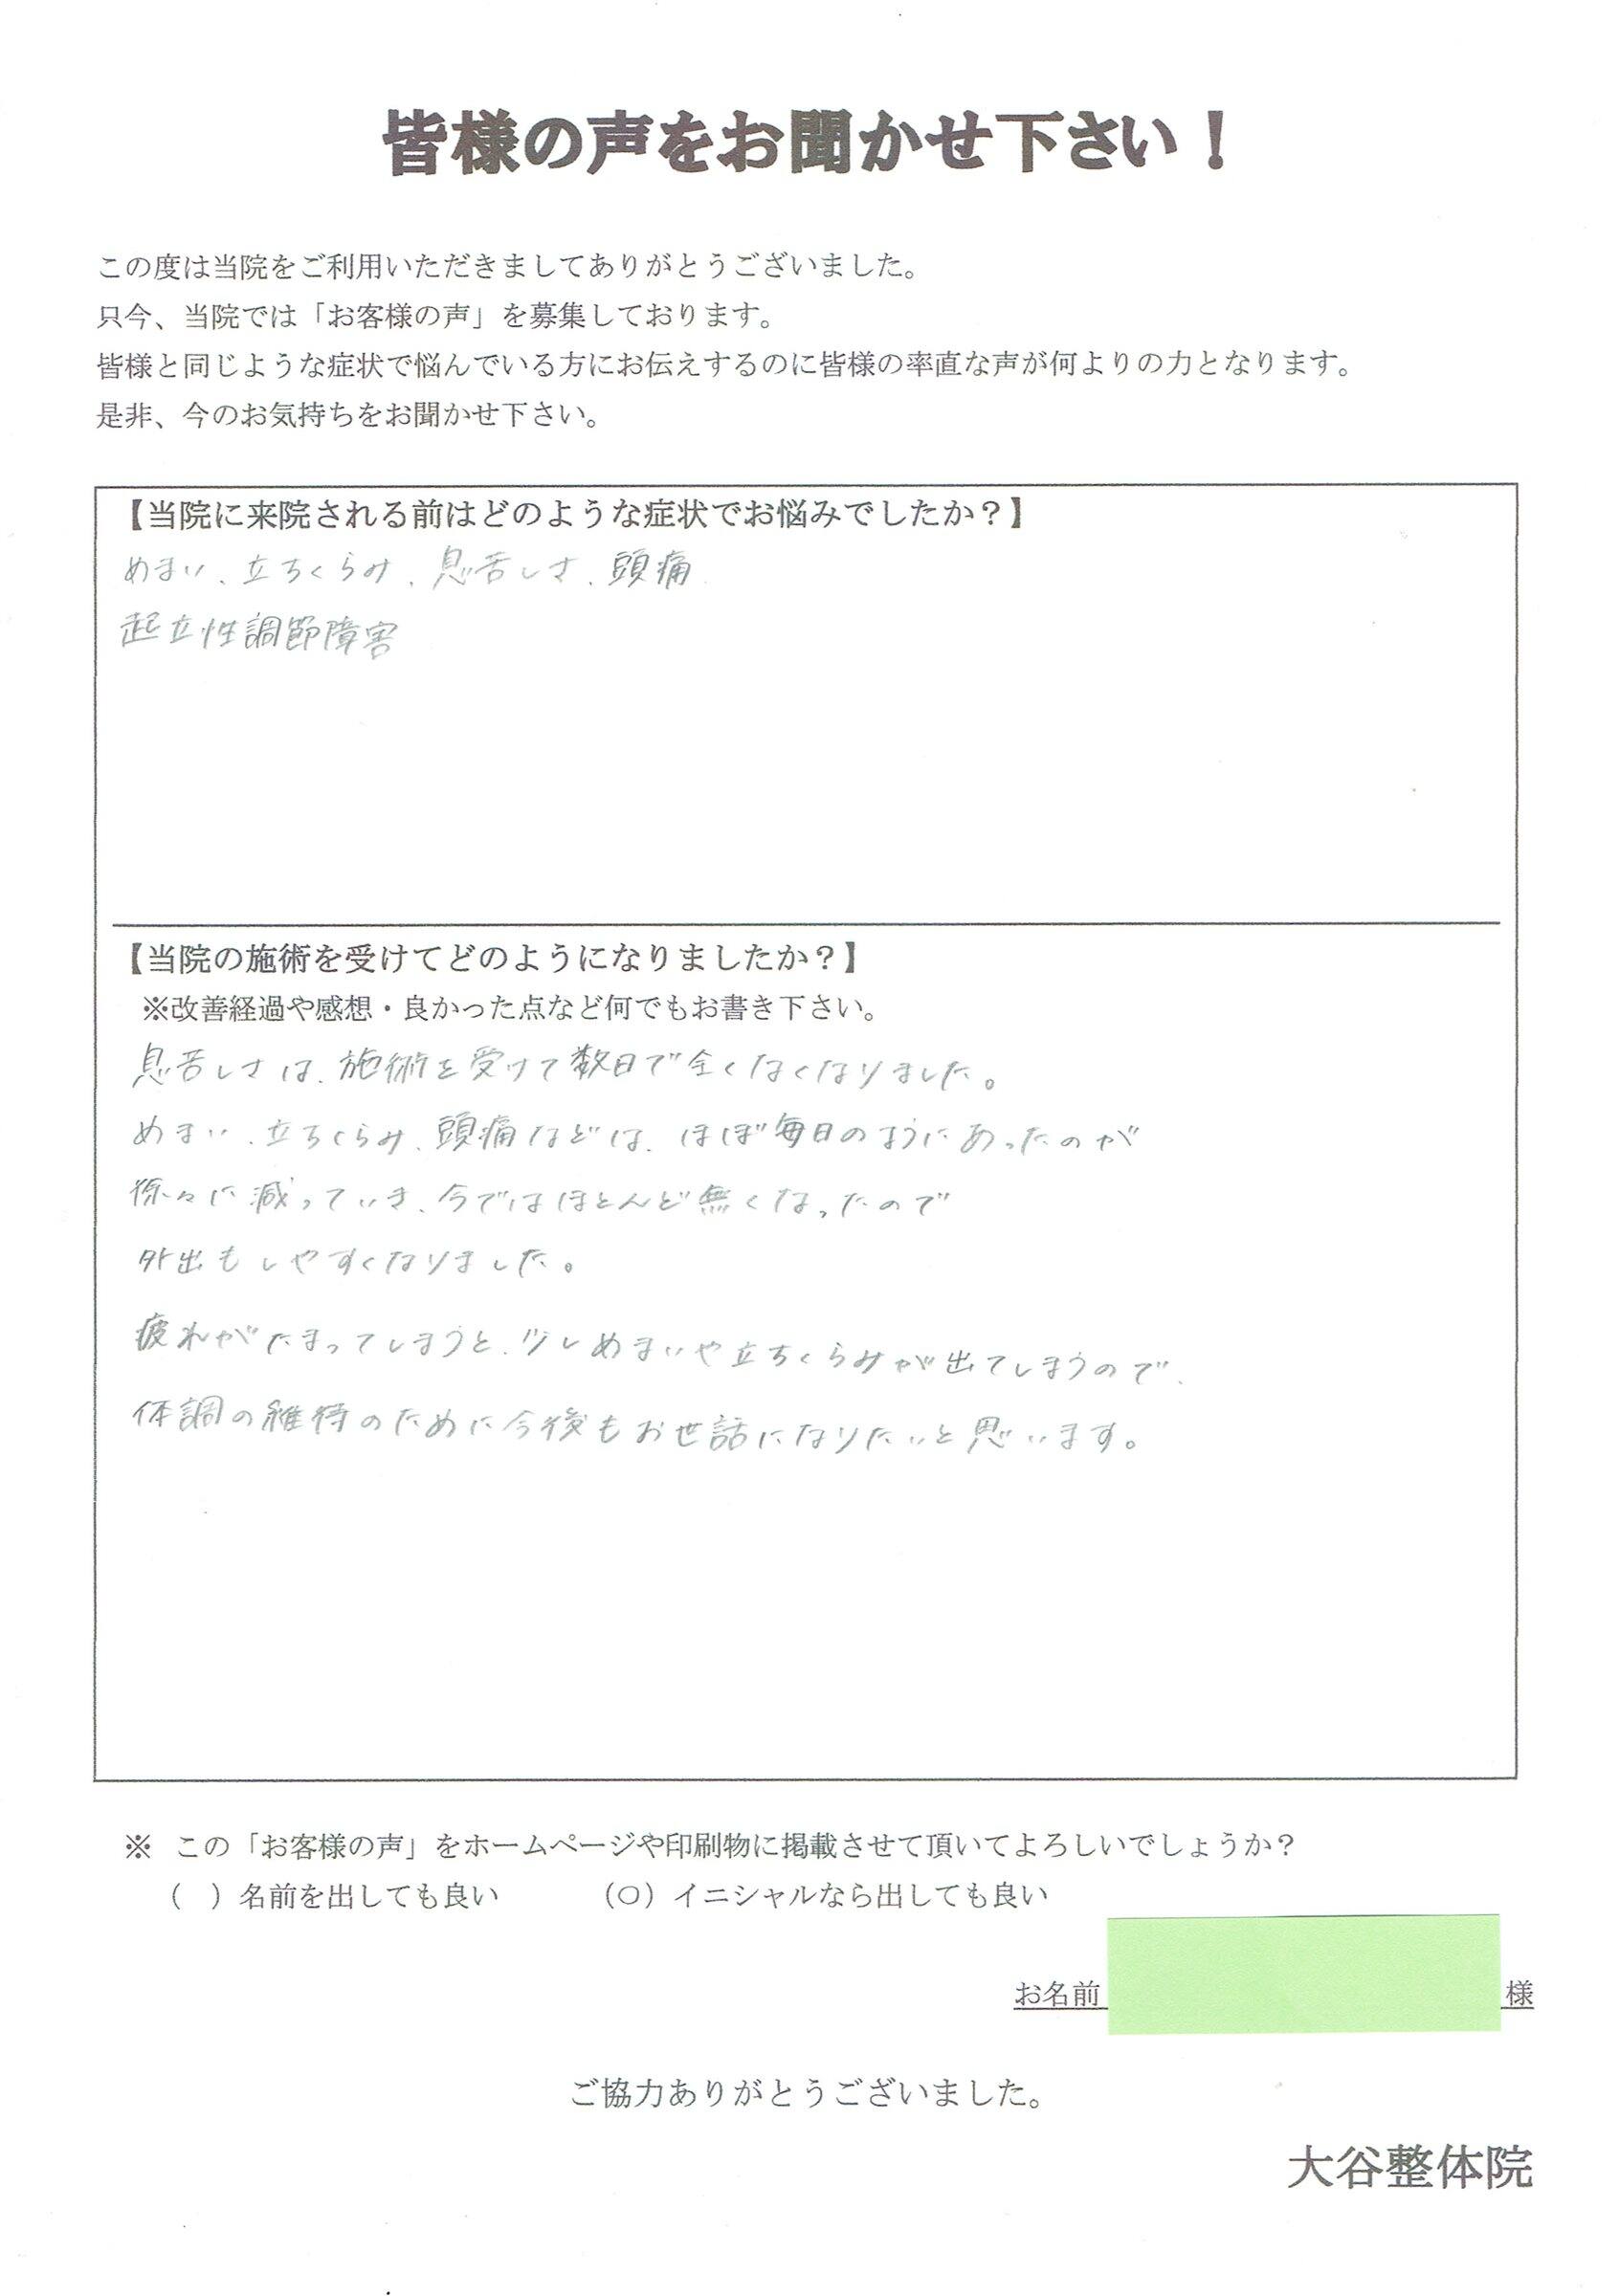

ほぼ毎日悩まされていた めまい、立ちくらみ、息苦しさ、頭痛が改善した HUさん

当院に来院される前はどのような症状でお悩みでしたか?

めまい、立ちくらみ、息苦しさ、頭痛

当院の施術を受けてどのようになりましたか?

息苦しさは施術を受けて数日で全くなくなりました。

めまい・立ちくらみ・頭痛などは、ほぼ毎日あったが徐々に減っていき、今ではほとんど無くなったので外出もしやすくなりました。

疲れが溜まってしまうと少しめまいや立ちくらみが出てしまうので、体調維持のために今後もお世話になりたいと思います。

※個人の感想であり、効果効能を保証するものではありません。